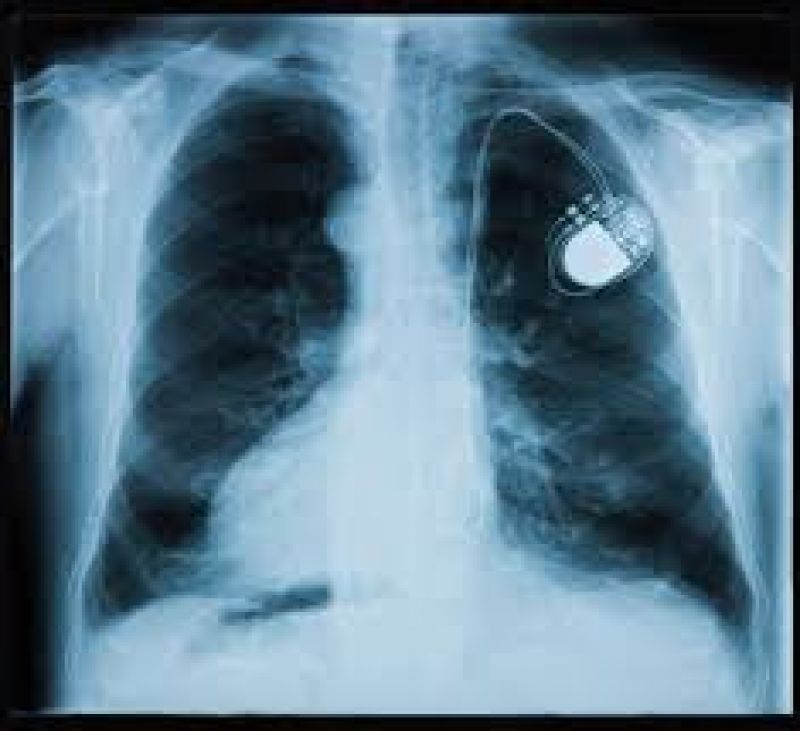

ਪੇਸਮੇਕਰ ਇਕ ਡਿਵਾਇਸ ਯਾਨੀ ਯੰਤਰ ਹੈ ਜੋ ਇਲੈਕਟ੍ਰੀਕਲ ਇਮਪਲਸ ਯਾਨੀ ਦਿਲ ਵਿੱਚ ਅਗਾਊ ਪੈਦਾ ਕਰਦਾ ਹੈ, ਇਸ ਦੀ ਮਦਦ ਨਾਲ ਦਿਲ ਦੀ ਧੜਕਨ ਅਤੇ ਆਵਾਜ਼ ਉਤੇ ਕਾਬੂ ਰੱਖਿਆ ਜਾ ਸਕਦਾ ਹੈ। ਉਂਝ ਤਾਂ ਇਸ ਦਾ ਇਸਤੇਮਾਲ ਦਿਲ ਨਾਲ ਜੁਡ਼ੀ ਕਈ ਸਮੱਸਿਆਵਾਂ ਲਈ ਕੀਤਾ ਜਾਂਦਾ ਹੈ, ਪਰ ਇਸ ਦੀ ਖਾਸ ਵਰਤੋਂ ਉਸ ਸਮੇਂ ਹੁੰਦਾ ਹੈ ਜਦੋਂ ਦਿਲ ਦੀ ਧੜਕਨ ਠੀਕ ਤਰ੍ਹਾਂ ਨਾਲ ਕੰਮ ਨਹੀਂ ਕਰਦੀ ਹੈ।

ਇਸਤੋਂ ਦਿਲ ਦੀ ਧੜਕਨ ਪ੍ਰਤੀ ਮਿੰਟ 60 ਵਲੋਂ 100 ਵਾਰ ਧੜਕਦੀ ਹੈ : ਪੇਸਮੇਕਰ ਬੈਟਰੀ ਦੀ ਮਦਦ ਨਾਲ ਕੰਮ ਕਰਨ ਵਾਲਾ ਯੰਤਰ ਹੈ ਜੋ ਦਿਲ ਦੀਆਂ ਧੜਕਨਾਂ ਨੂੰ ਨਿਯੰਤਰਿਤ ਰੱਖਣ ਵਿਚ ਮਦਦ ਕਰਦਾ ਹੈ। ਇਸ ਵਿਚ ਲੱਗੇ ਤਾਰ ਦਿਲ ਦੀ ਹਾਲਤ ਦੀ ਜਾਣਕਾਰੀ ਨੂੰ ਮਸ਼ੀਨ ਤੱਕ ਪਹੁੰਚਾਉਂਦੇ ਹਨ ਅਤੇ ਉਸ ਹਾਲਤ ਦੇ ਅਨੁਸਾਰ ਮਸ਼ੀਨ ਦਿਲ ਦੀ ਸਹਾਇਤਾ ਕਰਦੀ ਹੈ। ਇਸ ਵਿਚ ਲੱਗੀ ਬੈਟਰੀ ਜਨਰੇਟਰ ਵਿਚ ਸ਼ਕਤੀ ਪਹੁੰਚਦੀ ਹੈ ਅਤੇ ਇਹ ਸੱਭ ਇਕ ਪੇਸਮੇਕਰ ਪਾਕੇਟ ਬਾਕਸ ਵਿਚ ਇਕੱਠਾ ਹੁੰਦਾ ਹੈ। ਇਸ ਵਿਚ ਲੱਗੇ ਤਾਰ ਜਨਰੇਟਰ ਨੂੰ ਦਿਲ ਤੋਂ ਜੋਡ਼ਦੇ ਹਨ।

ਪੇਸਮੇਕਰ ਦਿਲ ਦੀਆਂ ਧੜਕਨਾਂ ਨੂੰ ਕਾਬੂ ਕਰਦਾ ਹੈ। ਜਦੋਂ ਦਿਲ ਦੀ ਧੜਕਨ ਅਸਾਧਾਰਣ ਹੁੰਦੀ ਹੈ, ਤਾਂ ਕੰਪਿਊਟਰ ਦੇ ਜ਼ਰੀਏ ਪਤਾ ਚੱਲ ਜਾਂਦਾ ਹੈ ਤੱਦ ਪੇਸਮੇਕਰ ਦਿਲ ਨੂੰ ਇਲੈਕਟ੍ਰੀਕਲ ਇਮਪਲਸ ਭੇਜਦਾ ਹੈ। ਇਹ ਇਮਪਲਸ ਪੇਸਮੇਕਰ ਦੇ ਤਾਰਾਂ ਨਾਲ ਜਾ ਕੇ ਅਸਧਾਰਣ ਧੜਕਨਾਂ ਉਤੇ ਕਾਬੂ ਪਾਉਣ ਦਾ ਕੰਮ ਕਰਦੇ ਹਨ।